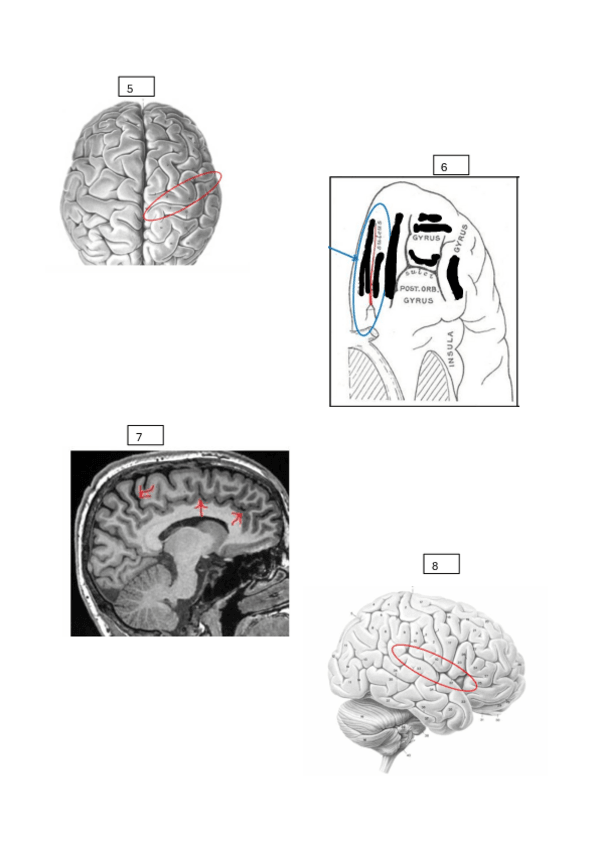

Acabo de publicar un pdf para el primer exámen de laboratorios de funciones con las fotos de los PowerPoints desordenadas para practicar para el exámen. Las respuestas están abajo del todo. Se separa en surcos/cisuras y giros ya que él lo preguntará así en el exámen. Suerte!

Fotos de las diapositivas desordenadas y sin nombres para practicar los surcos, cisuras y giros que entran en el exámen del primer laboratorio.